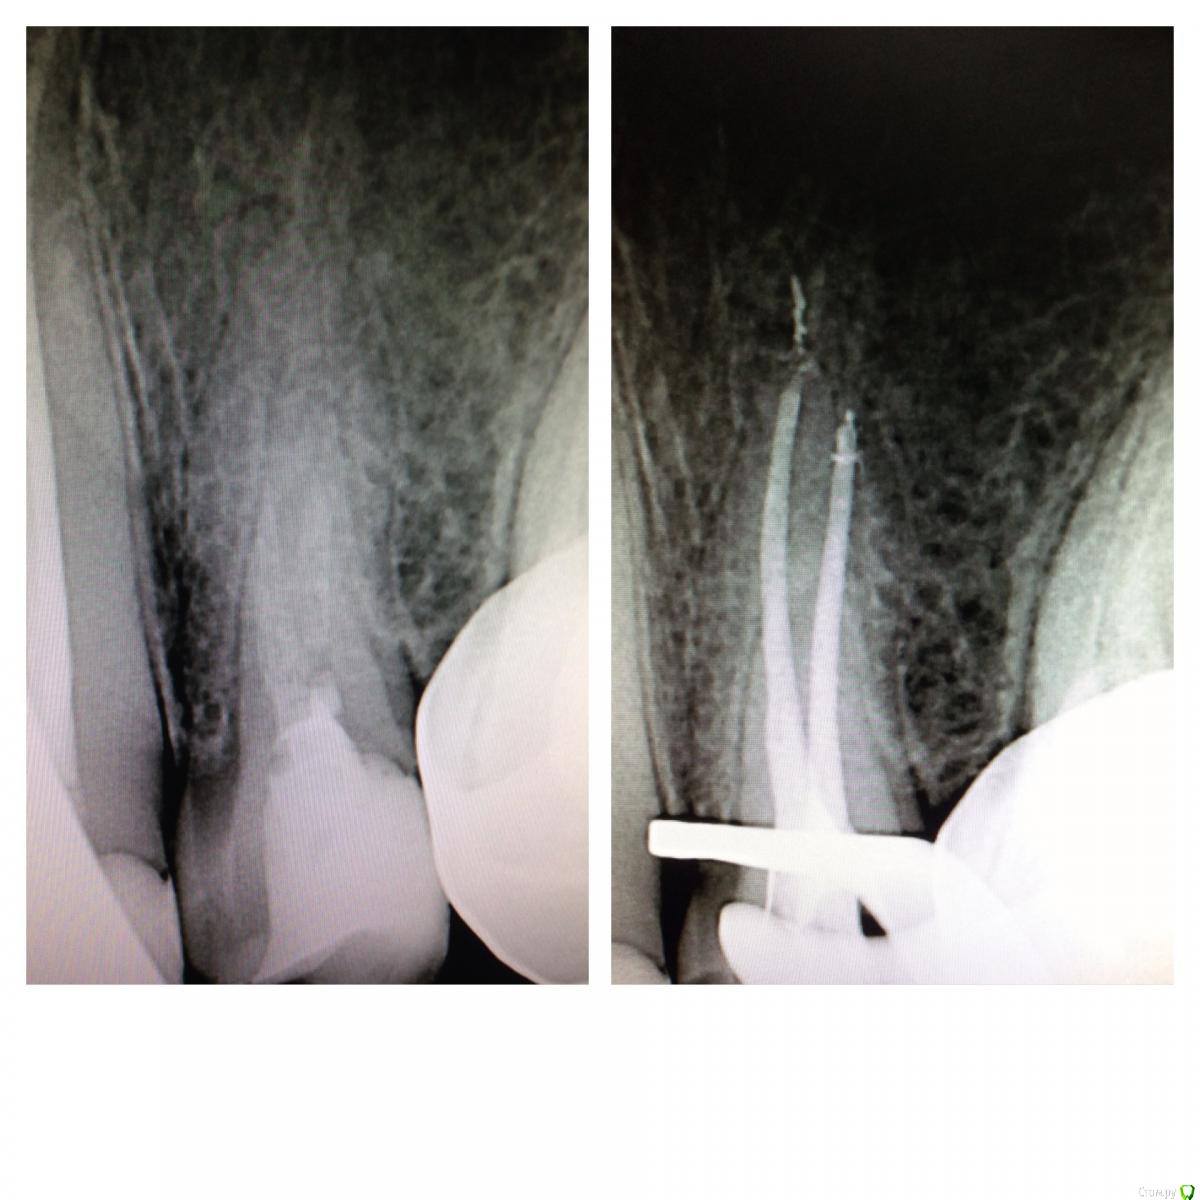

SSTi Опубликовано 19 января, 2015 Автор Поделиться Опубликовано 19 января, 2015 Так. Продолжение. 13 в предыдущем сообщении. Сегодня 15. Цемент. Или что-то подобное. Очень твердое. Изнурил меня зуб. 45 упор. Рд минус 1. 4 Ссылка на комментарий